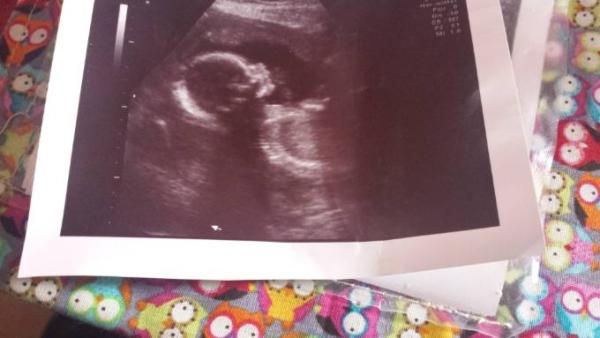

Das ist aber ein hübsches Bild! Bein Baby hat sich zu sehr an die Plazenta gekuschelt. Man erkennt nur Wirbelsäule und grob einen Kopf. Bei dir sieht man ja richtig Gesicht

Danke :) das hat meine auch erst gemacht. Der Doc hat sich aber echt Zeit genommen und sich richtig Mühe gegeben, um ein schönes Bild zu bekommen.